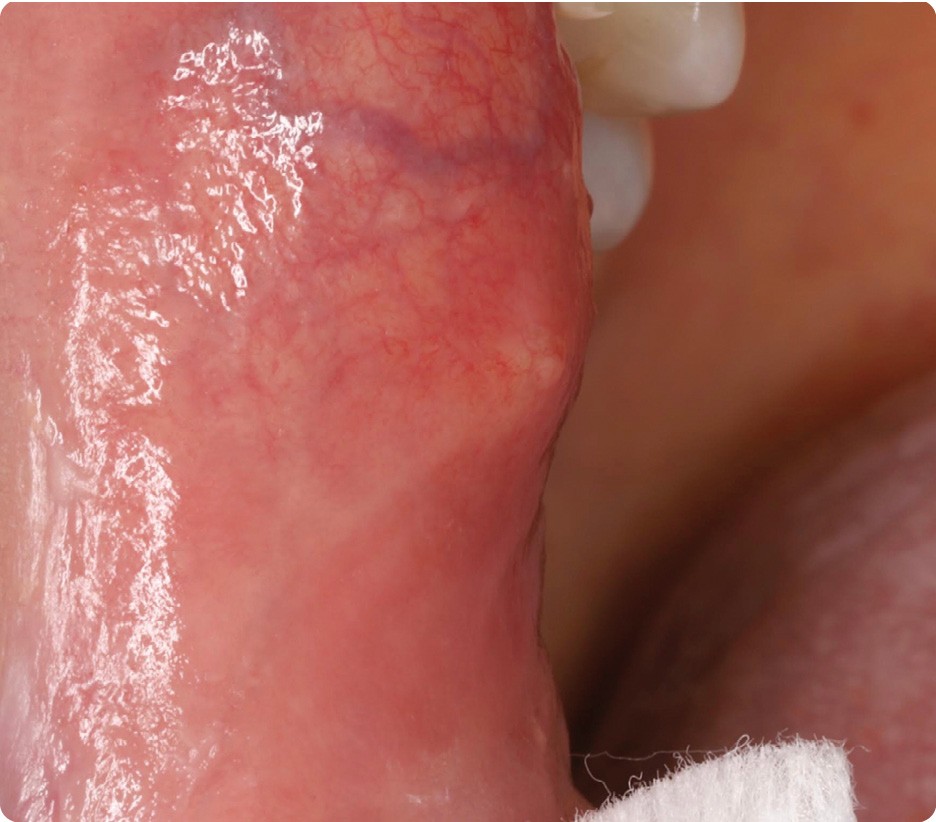

• La lésion siégeait dans la région rétro-commissurale droite, à 1 cm de la commissure, un peu au-dessus de la ligne occlusale. La mise sous tension de la muqueuse faisait apparaître, au centre de la plage érythémateuse, une petite zone jaunâtre. À la palpation, on percevait un nodule ferme, peu mobile, de 2 mm de diamètre environ.